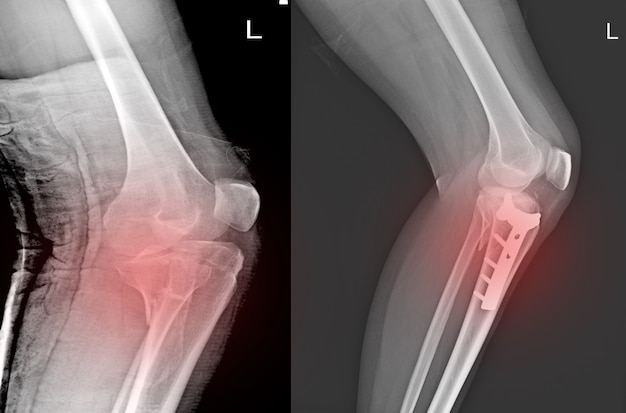

Как и при любой травме коленного сустава для постановки правильного диагноза выполняется рентгенография, на которой-то и можно увидеть перелом. Обычно рентгенографию выполняют в прямой и боковой проекциях, а для диагностики вертикальных переломов выполняют еще и осевую (аксиальную, или Merchant) проекцию.

Прямая (слева) и боковая (справа) проекции, на которых виден горизонтальный перелом надколенника со смещением отломков. Осевая проекция. Вертикальный перелом. Обратите внимание на возникшую в результате смещения ступеньку на скользящей поверхности надколенника.

Осевая проекция. Вертикальный перелом. Обратите внимание на возникшую в результате смещения ступеньку на скользящей поверхности надколенника.Иногда для более точного диагноза могут потребоваться компьютерная и/или магнитно-резонансная томография, но, в подавляющем большинстве случаев, достаточно рентгенографии.